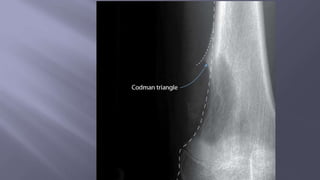

 plain radiograph: Imaging Findings

-Fracture line extending through a destructive lesion in the bone

Usually transverse in direction

-Surrounding bone may demonstrate

-Endosteal scalloping

-Cortical destruction

-Permeative pattern

-Frequently associated with a soft tissue mass

We should answer the Enneking's Four Questions for Bony Lesions

1. Where is the lesion located? Epiphysis , metaphysis , diaphysis

2. What is the lesion doing to the bone? transitional zone

3. What is the bone doing to the lesion? periosteal reaction

4. Dose anything suggest histology ? Calcification , ossification

 plain radiograph:Imaging Findings -Fracture line extending through a destructive lesion in the bone Usually transverse in direction -Surrounding bone may demonstrate -Endosteal scalloping -Cortical destruction -Permeative pattern -Frequently associated with a soft tissue mass

We should answerthe Enneking's Four Questions for Bony Lesions 1. Where is the lesion located? Epiphysis , metaphysis , diaphysis 2. What is the lesion doing to the bone? transitional zone 3. What is the bone doing to the lesion? periosteal reaction 4. Dose anything suggest histology ? Calcification , ossification